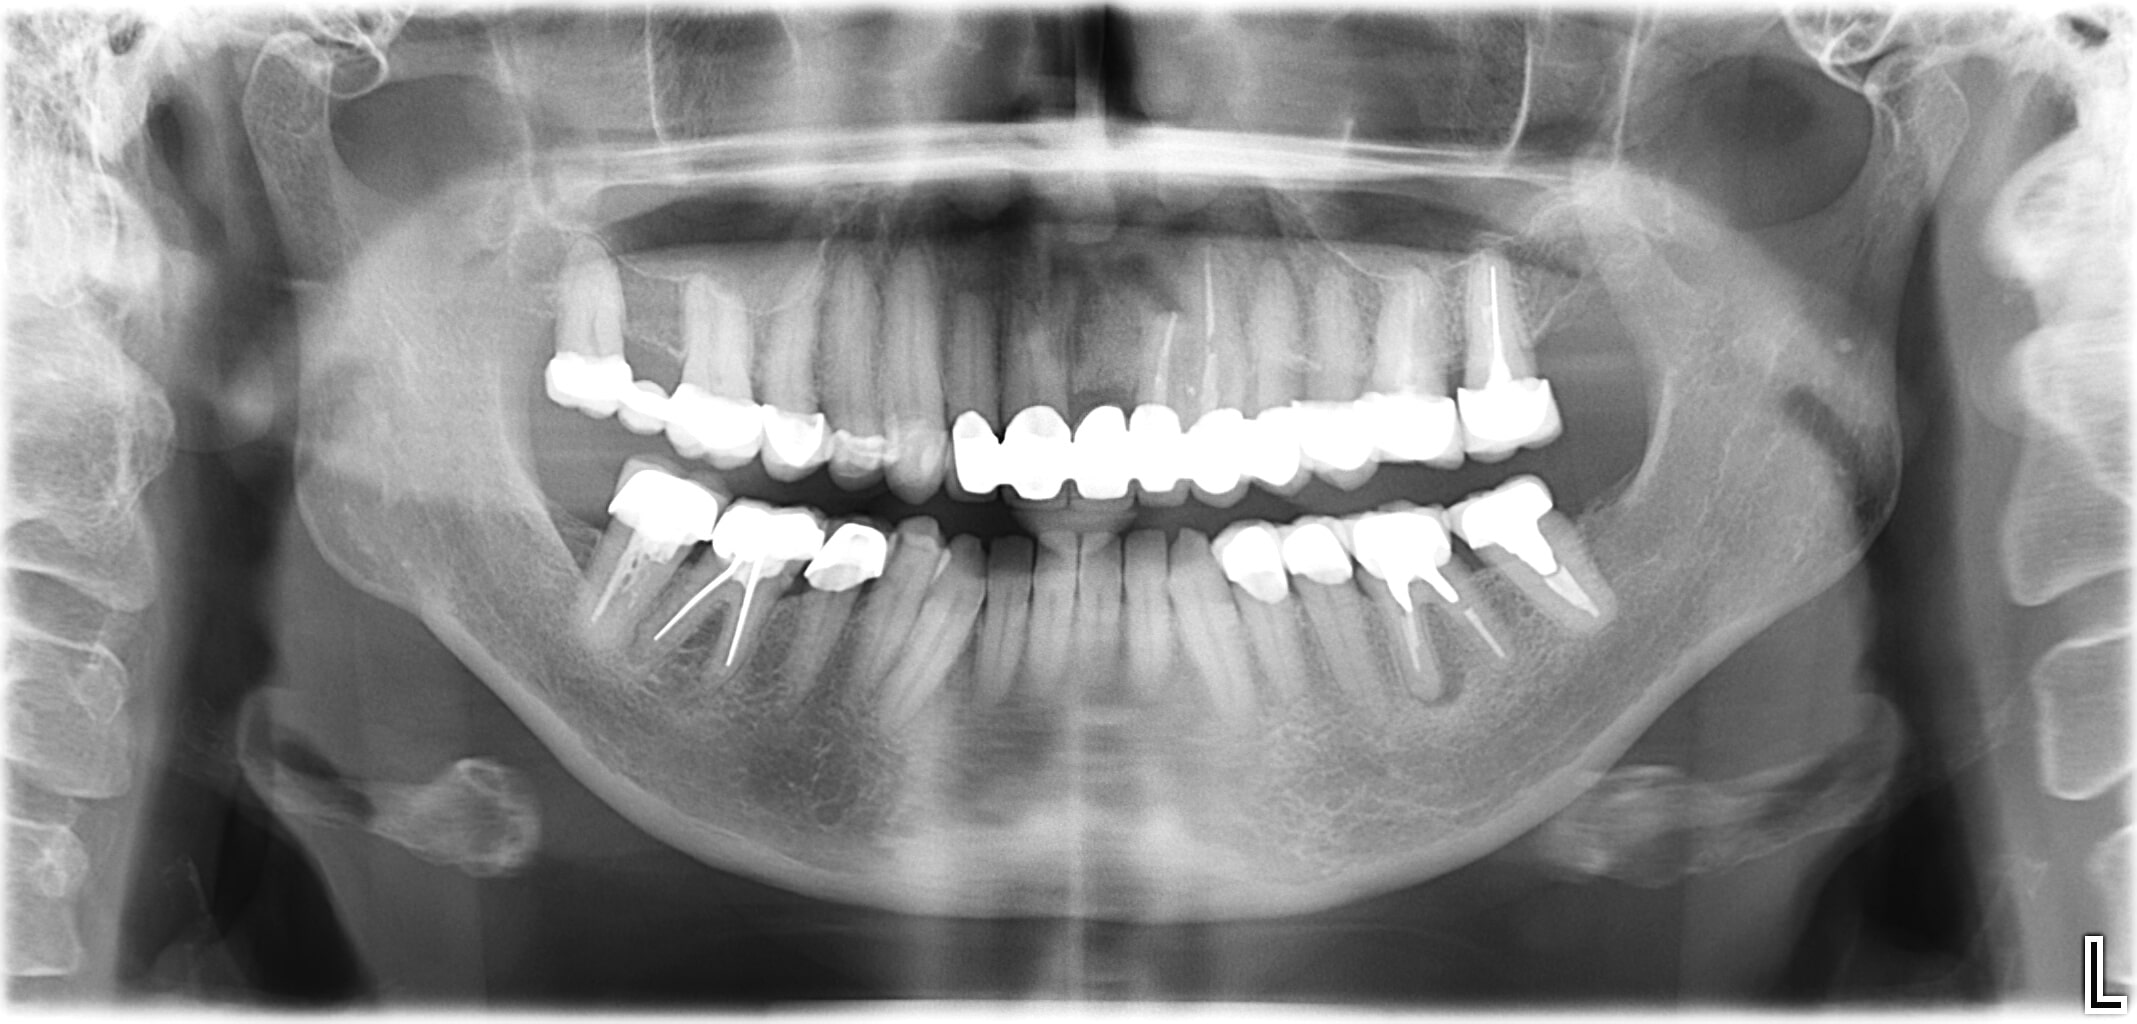

Wenn am Ende der Zahnreihe Zähne fehlen, muss eine herausnehmbare Prothese hergestellt werden. Für eine festsitzende Prothese wäre ein hinterer „Pfeiler“ zur Befestigung nötig. Durch den Einsatz von Implantaten kann man auf den herausnehmbaren Zahnersatz verzichten. Das bringt Vorteile beim Kauen und hilft bei der Vorbeugung funktioneller Gelenkerkrankungen.

- Am Ende der Zahnreihe fehlen ein oder mehrere Zähne

- Natürliche Zähne begrenzen den zahnlosen Abschnitt nur auf einer Seite

- Ein zahngetragener Zahnersatz (Brücke) ist nicht möglich

- Versorgung in der klassischen Zahnersatzkunde: Teilprothese abnehmbar

Die Lösung

- Eine rein implantatgetragene Verbundbrücke oder Einzelzahnimplantate vermeiden Brücken und abnehmbare Teilprothesen.

- Implantate als zusätzliche Pfeiler: Brücke auf natürlichen Zähnen und Implantaten